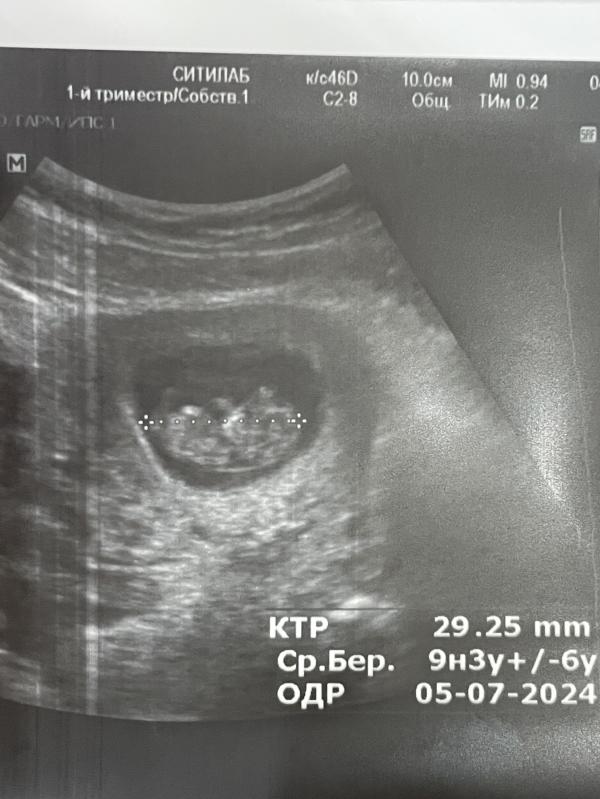

Мои колики переодические внизу живота обусловили по узи гипертонусом (но его еще неделю назад поставили), и большими яичниками после очередного свежего протокола (до сих пор 55 и 51 мм, но уже меньше, были 67 и 64🫣), плюс желтое тело слева…. Пью магний дальше🤪 Что порадовало-моя гематома уже ушла, от нее остался только след🥳 главное с малышом все хорошо, лежит там ручками и ножками болтает во всю, так это мило, я засняла на видео для нашего папы, и как всегда фото выдали щекастенького моего🥹🥰 сегодня 9.3 по ктр, расти малыш крепким и здоровым🥰😘

Да, там такие щечки пухляшики, животик сладкий, ручки, ножки-все видно, а он всего 3 см😅